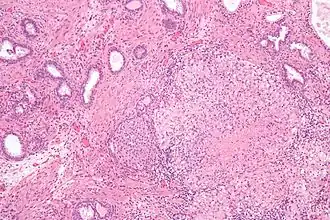

Гистопатологические находки при гранулёматозном простатите

При гистологическом исследовании биоптата ткани предстательной железы больного гранулёматозным простатитом обнаруживается значительная деструкция ацинарных протоков предстательной железы, инфильтрация предстательной железы эпителиоидными клетками, гигантскими клетками, лимфоцитами, плазматическими клетками и гистиоцитами, а также плотный фиброз (разрастание соединительной ткани и замещение ткани предстательной железы соединительной тканью).